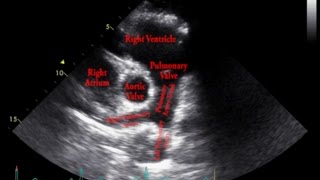

Gulfcoast Ultrasound Institute Instructor Emily Downs, BS, RDMS, RVT, RDCS, RT demonstrates how to evaluate the bifurcation of the aorta at the level of the distal aorta using ultrasound.